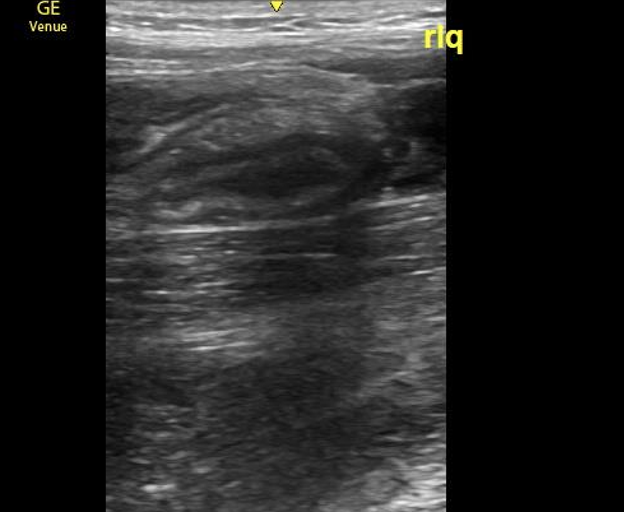

A 14-year-old female with a past medical history of anxiety and bipolar disorder presented to the emergency department with constant, sharp, non-radiating right lower quadrant abdominal pain. The pain began suddenly two nights ago and worsened with movement. She denied nausea, vomiting, diarrhea, fevers, or chills. On physical exam, her abdomen was tender to palpation in RLQ and RUQ with rebound and guarding. Labs demonstrated a leukocytosis of 12.9k with no other remarkable abnormalities. Given the broad differential of appendicitis vs ovarian torsion vs gallbladder disease, bedside ultrasound was performed. A non-compressible dilated appendix 7.3mm in diameter with an appendicolith present. (Image 1) Comprehensive radiology ultrasound of the abdomen demonstrated a non-peristalsing 6.5 x 1.1 x 1.6 cm tubular structure in the right lower quadrant concerning probable appendicitis. General surgery was consulted, and the patient underwent a laparoscopic appendectomy the same day. She underwent the procedure without complication and was discharged the following day.

Image 1. Image from case showing a dilated appendix suggestive of acute appendicitis with appendicolith and target sign present.

Image 7. Normal appendix, longitudinal view; appendix ending in blind pouch

When appendicitis is present, the appendix will measure greater than 6 mm from outer wall to outer wall, with a wall thickness greater than 3 mm and lack compressibility. (Images 1, 8, and 9) (Remember, you may want to do these measurements after you have obtained your images, given your patient a high five and a sticker, and stepped aside to perform measurements on the machine.) An inflamed appendix can demonstrate a “ring of fire” with enhanced color flow. Secondary findings you may see include: an appendicolith, (Image 1), periappendiceal free fluid (Image 10), a target sign (Image 1), enlarged mesenteric lymph nodes, thickening and hyperechogenicity of the overlying peritoneum (Image 8), dilated and hypoactive small bowel, and thickening of the apical cecal pole.